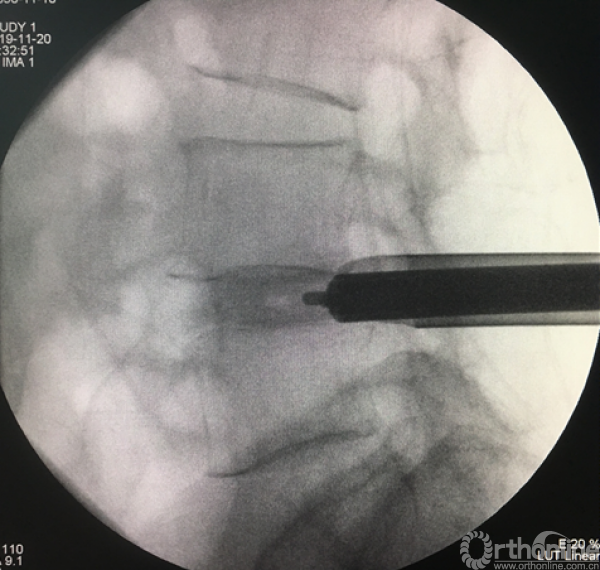

正侧位透视观察滑脱是否复位、融合器及植骨的位置

植入EndoPIN,运用扩张管、克氏针以及动力电钻等工具

植入经皮椎弓根钉并加压